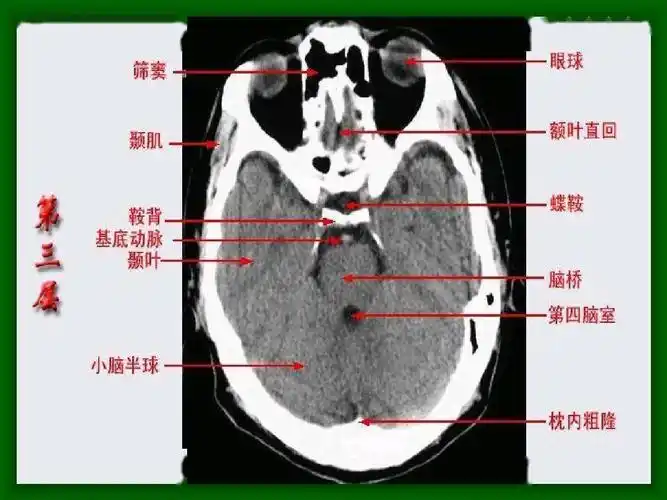

头部ct影像解剖

头颅ct 解剖图谱,人手一份